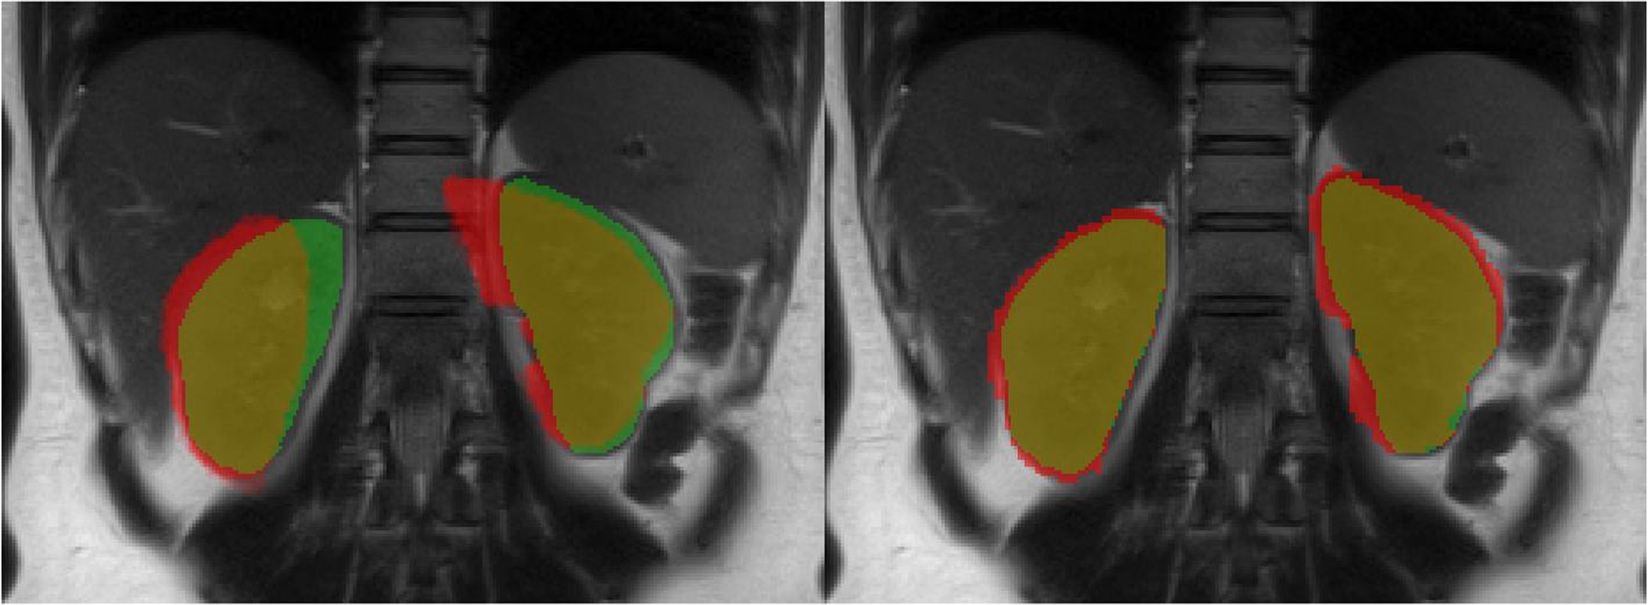

Figure 6

Comparison of kidney segmentation results obtained from the b0-image without processing (left) and with topup-s2v pipeline (right) overlaid on HASTE image. Green and red pixels correspond to the mask obtained from HASTE and b0-image, respectively. Pixels in yellow colour represent the overlap between masks from HASTE and b0-image.